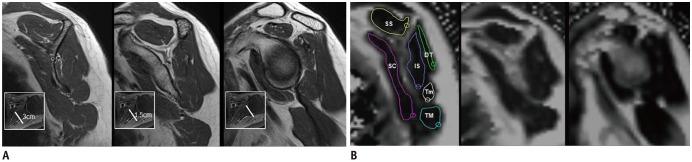

Twenty-four patients with clinical diagnoses of adhesive capsulitis and either intact rotator cuffs or Ellman grade 1 partial tears as indicated by MRI scans were included. Two radiologists independently evaluated MRI scans of adhesive capsulitis as follows: presence or absence of axillary recess capsular and extracapsular hyperintensities; thickness of the coracohumeral ligament; thickness of abnormal rotator interval soft tissue; and thickness of glenoidal/humeral axillary recess capsules. Fat quantifications of the supraspinatus, infraspinatus, teres minor, subscapularis, teres major and posterior deltoid muscles were performed using multi-echo Dixon imaging at three locations. Inter-rater agreement was assessed. Differences in fat percentages were assessed and correlations between fat percentages and quantitative measurements were evaluated.

本研究纳入了 24 例临床诊断为粘连性肩关节囊炎且 MRI 检查显示肩袖完整或 Ellman 分级为 1 级部分撕裂的患者。两位放射科医生独立评估了粘连性肩关节囊炎的 MRI 表现,包括腋窝隐窝和囊外高信号的存在或不存在、喙肱韧带厚度、异常肩袖间隙软组织厚度和盂肱腋窝隐窝囊厚度。使用多回波 Dixon 成像在三个部位对冈上肌、冈下肌、小圆肌、肩胛下肌、胸大肌和后三角肌的脂肪含量进行定量分析。评估了观察者间的一致性。评估了脂肪百分比的差异,并评估了脂肪百分比与定量测量值之间的相关性。